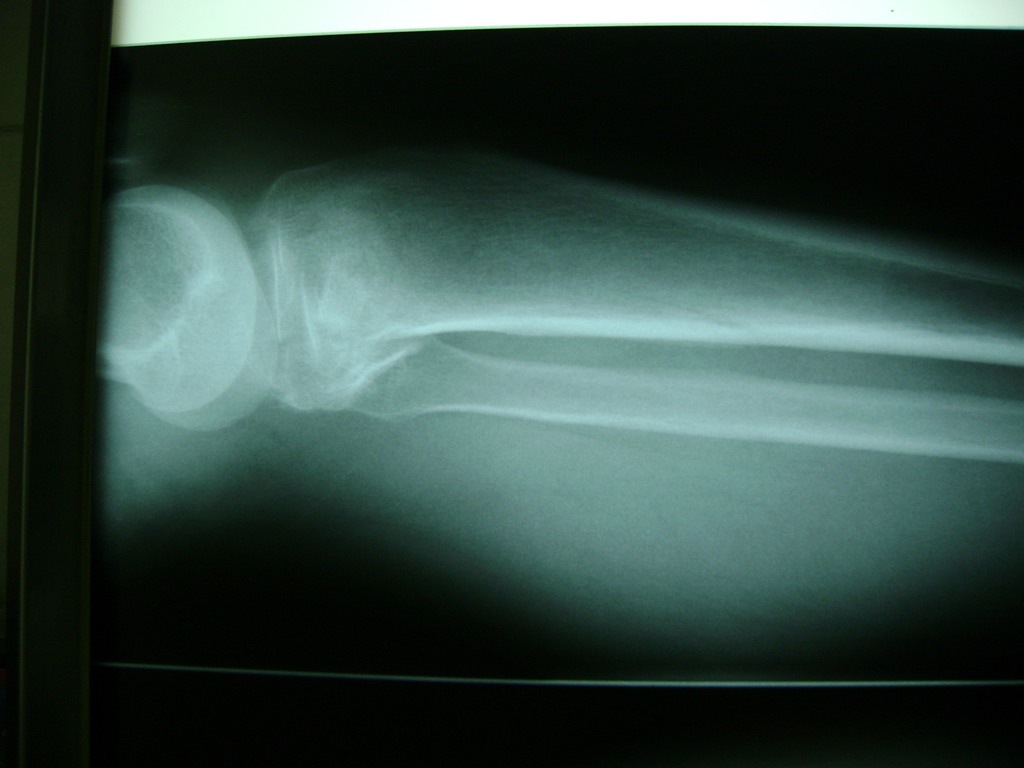

Cirugías de Codos - Rodilla

La artroscopia de rodilla es un cirugía en el cual la estructura interna de la articulación es examinada ya sea para realizar un diagnostico o para realizar un tratamiento, este procedimiento se realiza utilizando un instrumento parecido a un pequeño tubo llamado artroscopio.